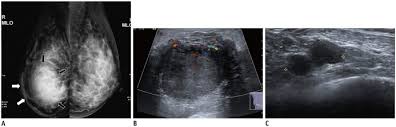

What Does Inflammatory Breast Cancer Look Like On Ultrasound / Benign And Malignant Characteristics Of Breast Lesions At Ultrasound Radiology Reference Article Radiopaedia Org : Ultrasound is useful for looking at some breast changes, such as lumps (especially those that can be felt but not seen on a mammogram) or changes in women with dense breast tissue.. Unlike typical breast cancer, ibc usually cannot be detected by a mammogram or ultrasound. What does breast cancer look like on a mammogram? Inflammatory carcinoma of the breast, also referred to as inflammatory breast cancer, is a relatively uncommon but aggressive form of invasive breast carcinoma with a characteristic clinical presentation and unique radiographic appearances. I need some knowledge about ibc. My last breast ultrasound was december.

Did not respond to antibiotic and was referred for biopsy. Inflammatory breast cancer develops when cancer cells block lymph vessels. We'll show you breast cancer pictures to help you identify any physical traits of the condition. The aim of this study was to evaluate the features of inflammatory breast carcinoma (ibc) on mri compared with mammography and ultrasound and to better define the role of mri in patients with this aggressive disease. Online says it develops suddenly.

Early warning signs of inflammatory breast cancer along with images of inflammatory breast cancer are mentioned below. Does this look like inflammatory breast cancer? Unlike typical breast cancer, ibc usually cannot be detected by a mammogram or ultrasound. Ultrasounds are useful for detecting signs of breast cancer even after a mammogram comes back negative. Googled and freaking out about ibc. The usual cause of inflammatory breast symptoms is breast mastitis or duct ectasia. The breast tissue deflects these waves causing echoes, which a computer uses to paint a picture of what's going on inside the breast tissue (no radiation is involved). In view of those symptoms often occur, and errors in diagnosis of patients treated for inflammatory diseases, that happen to be named and are known as these forms breast cancer.

Did not respond to antibiotic and was referred for biopsy. Inflammatory breast cancer is often misdiagnosed because it is so rare, and is difficult to treat because it is particularly aggressive. What does breast cancer look like on a mammogram? However, inflammatory breast cancers are more likely to show solid mass lesions. My last breast ultrasound was december. As these inflammatory breast cancer picture shows, the texture of the breast may change and appear to look dimpled or ridged, like an orange peel. The woman who has inflammatory breast cancer has breast cancer that's red and inflamed, with an angry look to the breast cancer, he says. The problem is that inflammatory breast cancer can look very much like mastitis early on, and is often diagnosed only after a woman has been treated first for mastitis (often with no improvement in symptoms). What does breast cancer look like? I need some knowledge about ibc. These tubes, which are hollow, allow lymph fluid to drain out of the breast. I have inflammatory breast cancer which was firstly diagnosed as mastitis in jan 09. Women or men who develop any of the inflammatory breast cancer early signs should seek medical care immediately to ensure timely treatment.

It's called inflammatory because that's how it looks. Any area that does not look like normal tissue is a possible cause for concern. Inflammatory breast cancer, also known as carcinomatous mastitis, t4d, or pev 2 or 3, is the only real therapeutic emergency in breast oncology, given the high risk of metastasis, the reason for the most unfavourable prognosis of all breast cancers.it must consequently be diagnosed rapidly, and imaging examinations must in no case delay therapeutic management. Because ibc grows quickly, it is usually found at a locally advanced stage, meaning that cancer cells have spread into nearby breast tissue or lymph nodes. A breast ultrasound is a scan that uses penetrating sound waves that do not affect or damage the tissue and cannot be heard by humans. Ultrasound is useful for looking at some breast changes, such as lumps (especially those that can be felt but not seen on a mammogram) or changes in women with dense breast tissue. As these inflammatory breast cancer picture shows, the texture of the breast may change and appear to look dimpled or ridged, like an orange peel. Their differences, however, lie in their enhancement.

However, inflammatory breast cancers are more likely to show solid mass lesions. The problem is that inflammatory breast cancer can look very much like mastitis early on, and is often diagnosed only after a woman has been treated first for mastitis (often with no improvement in symptoms). This condition usually does not develop a lump, but commonly affects the breast skin. The aim of this study was to evaluate the features of inflammatory breast carcinoma (ibc) on mri compared with mammography and ultrasound and to better define the role of mri in patients with this aggressive disease. These tubes, which are hollow, allow lymph fluid to drain out of the breast.